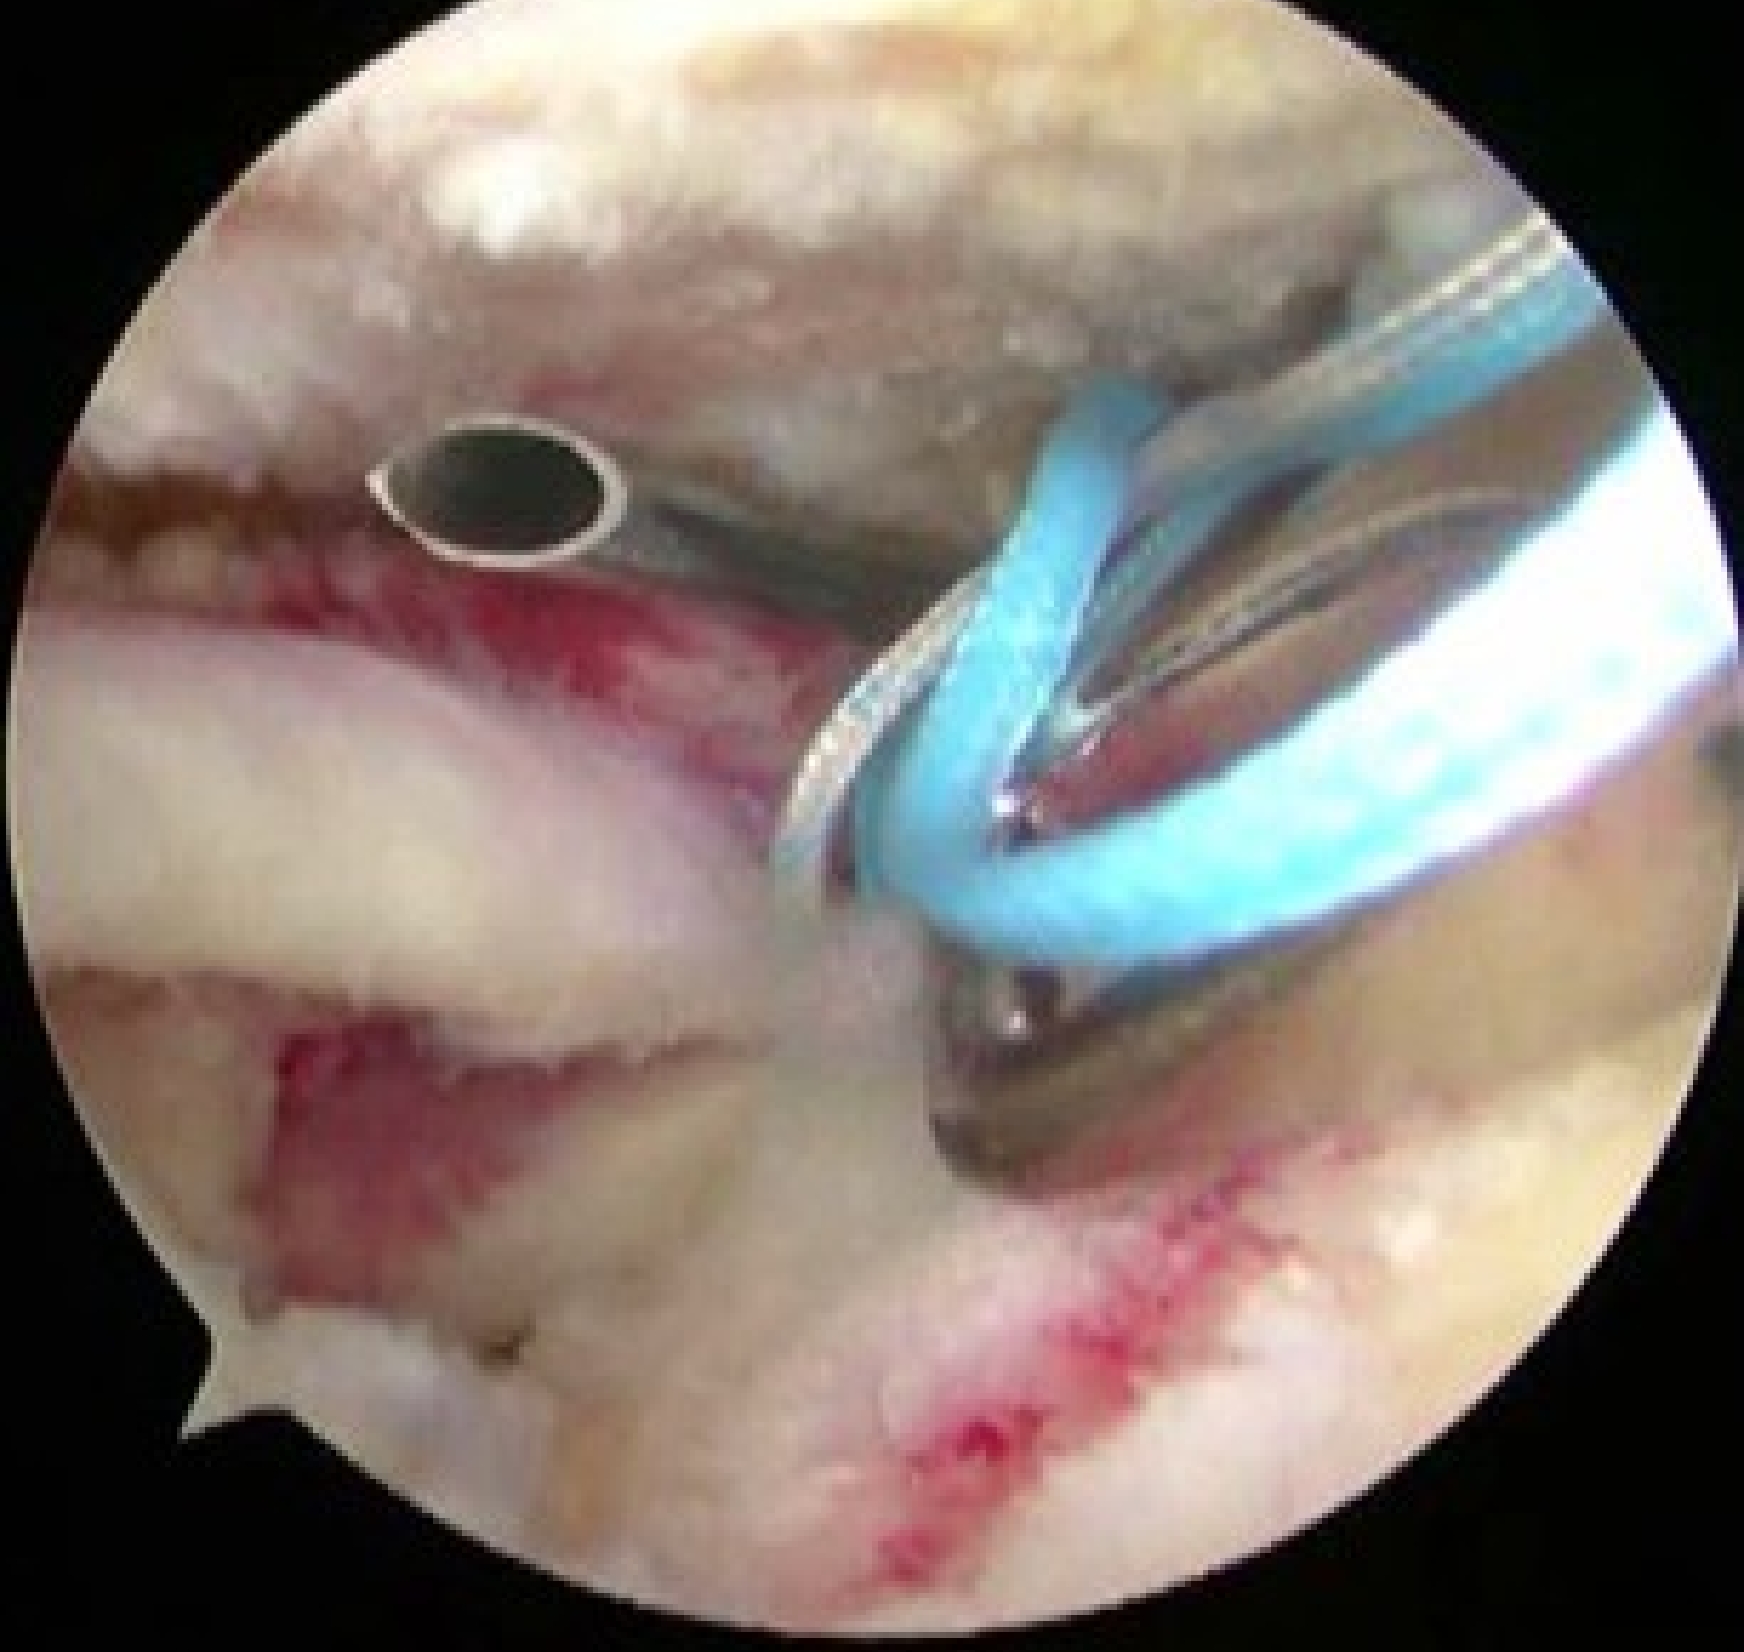

内側アンカー設置

吸収性アンカー(直径4.5から5.5mm)

器具を使用して腱板に糸をかける

外側アンカー設置